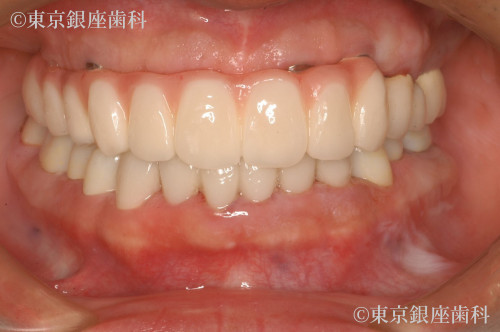

Before

After